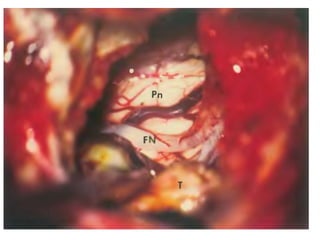

Fig. 26a, b Right side. The root fibers of the hypoglossal

nerve (12) collect in two bundles, which pierce the dura in

two dural pori. The hypoglossal nerve is situated more anteriorly

and medially than the root fibers of the lower cranial

nerves. The arterial relationship is the vertebral artery, with

perforating arteries to the brain stem. The curved vertebral

artery displaces and stretches the hypoglossal nerve fibers.